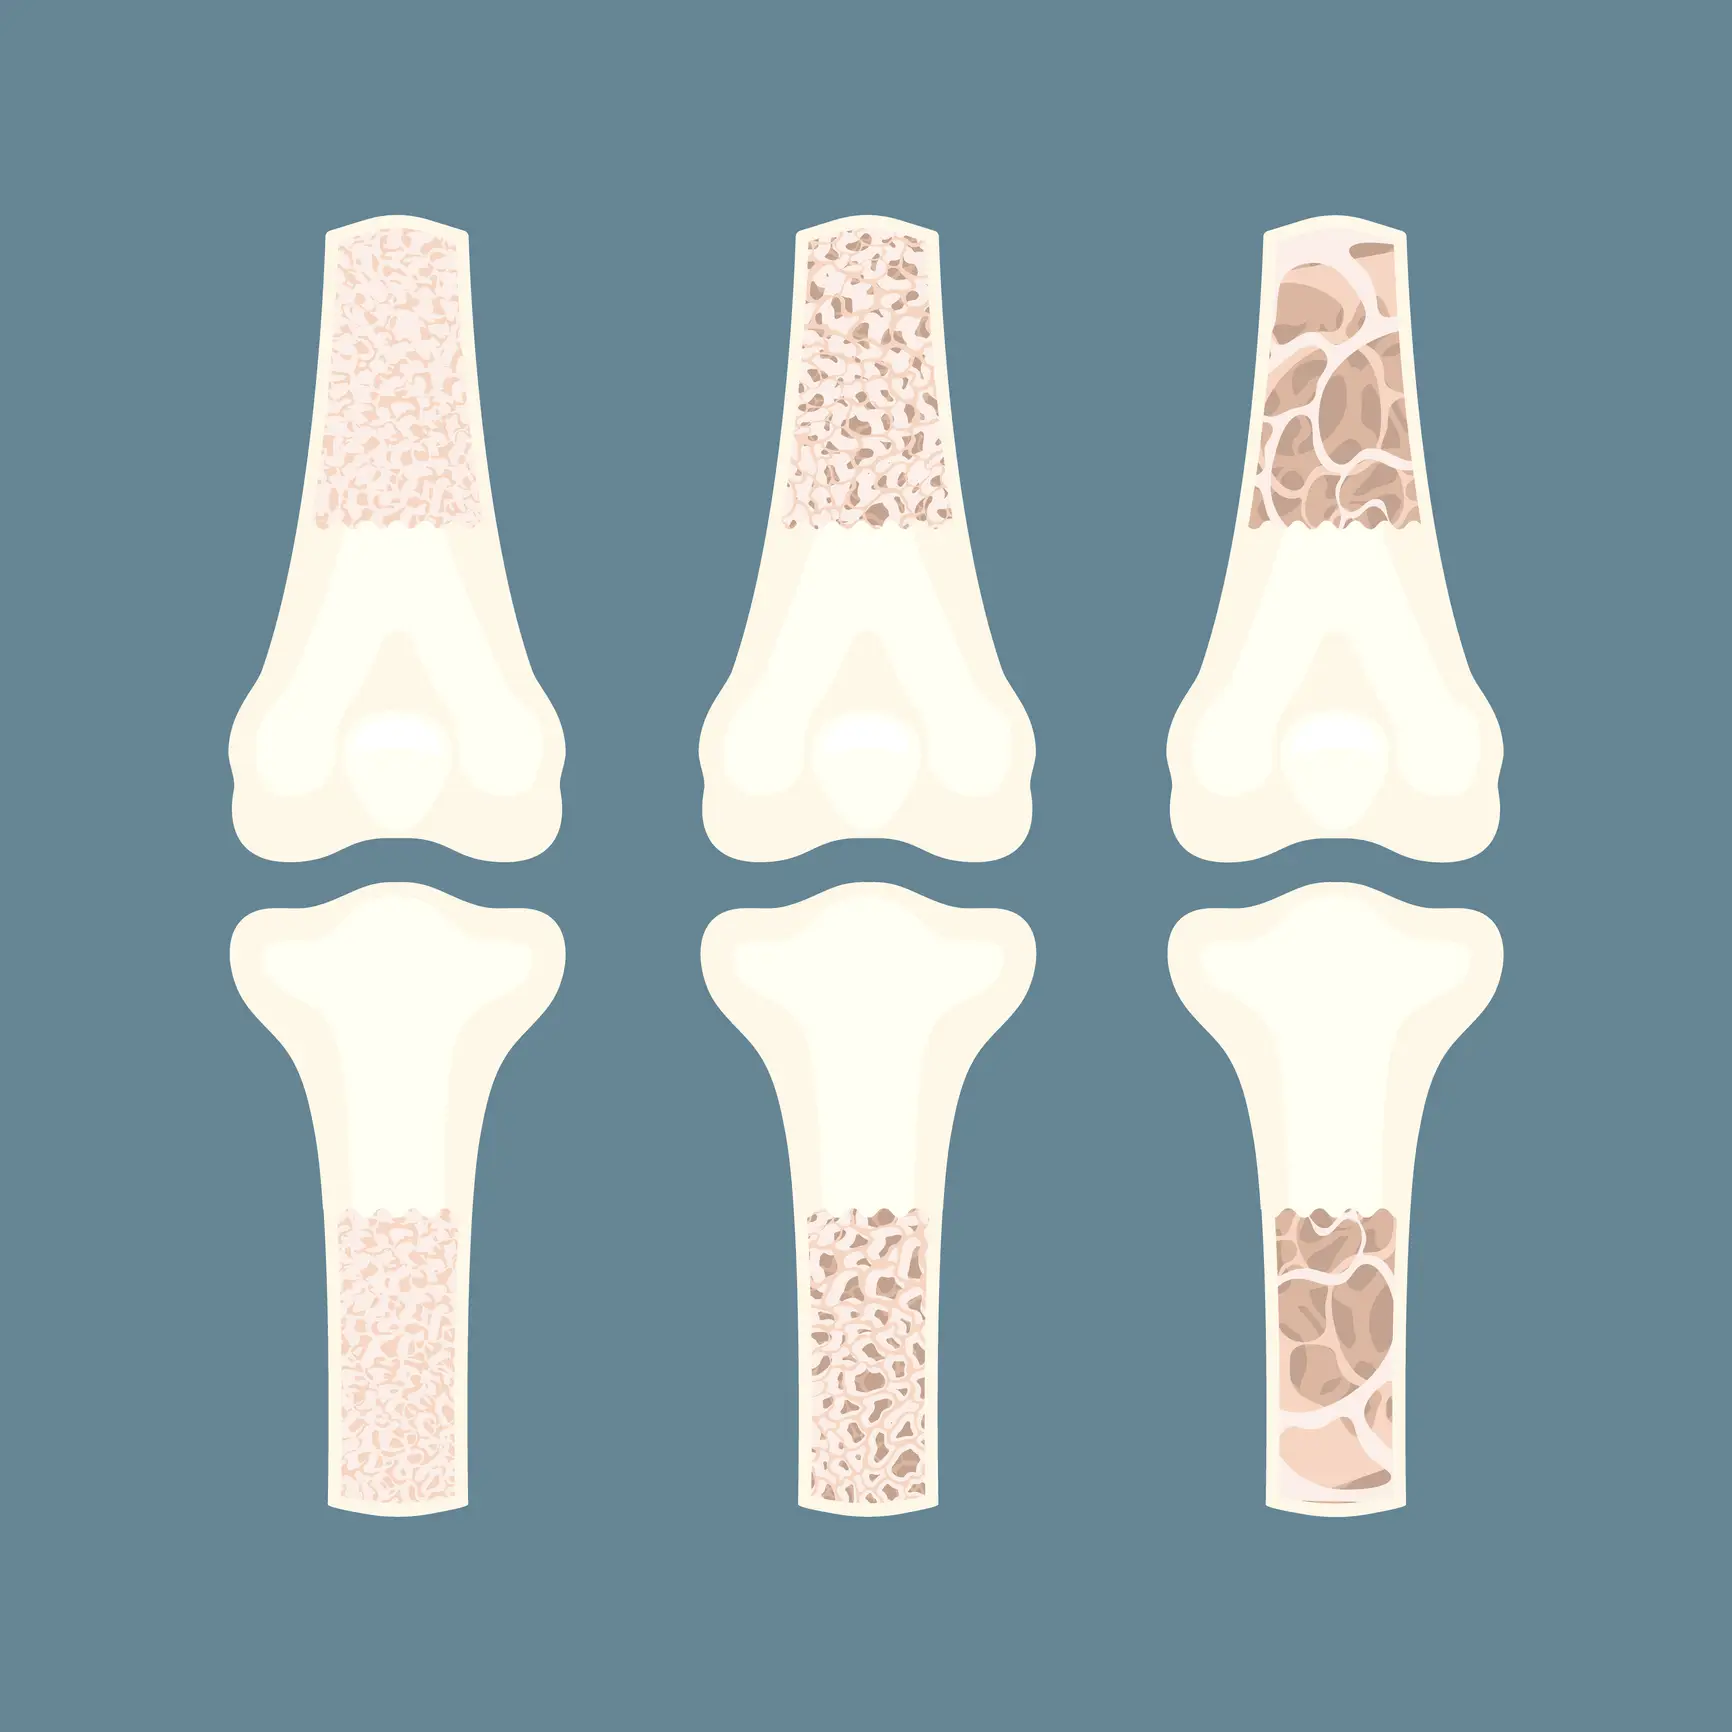

This is a finding which the Royal Osteoporosis Society (ROS) agrees with, as the size and strength of your skeleton can impact your likelihood of developing weaker bones.

Age is another important factor. The ROS notes that a person's bone density begins to decline after the age of 30, with women who've been through the menopause at a particular risk of developing brittle bones or osteoporosis.